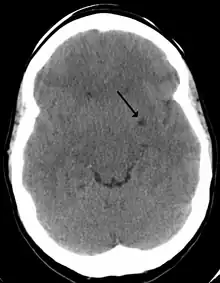

Espace LCR de Virchow-Robin en 2010.

Les espaces de Virchow-Robin, encore appelés espaces périvasculaires, doivent leur nom à Rudolf Virchow et Charles Philippe Robin. Ce sont des espaces, souvent uniquement virtuels, qui entourent les vaisseaux sanguins pendant une courte distance alors qu'ils entrent dans le cerveau. Ces espaces se trouvent donc entre d'une part la paroi des vaisseaux et d'autre part l'intima pia qui est la couche avasculaire de la pie-mère. Ils forment des sortes de gaines, sous arachnoïdienne et sous piale, entourant les artérioles pénétrant dans le cortex, et remplies de LCR.